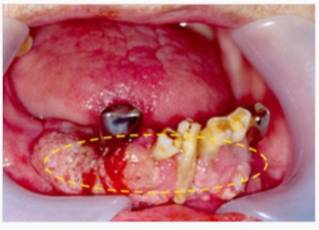

초기 구강암의 경우 구내염과 혼동되는 경우가 많다. 둘 다 입안 점막에 병변이 발생하는데 그 모양이 '하얗게 헐어 있는 모습'으로 비슷해서다. 구강암 초기엔 통증도 적어, 환자 스스로가 단순 염증으로 치부했다가 암 치료가 늦어지는 경우도 많다.

구내염은 대부분 7일, 길어도 10일 이내 자연적으로 치유된다. 반면 구강암은 특별한 이유 없이 같은 부위에서 반복적으로 발생하거나, 3주 이상 상처가 낫지 않고 점점 커진다. 이영찬 교수는 "특히 구강 점막에 하얗거나 붉은 반점(백반·홍반)이 생긴 경우, 틀니·보철물 주변에 상처가 반복된다면 반드시 전문의 진료를 받아야 한다"고 조언했다.